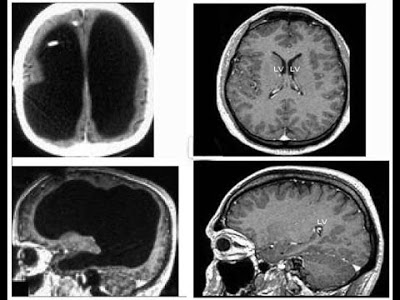

À Esquerda, Indivíduo Com Pequena Parte de um Cérebro (em Cinza), à Direita, Indivíduo com Cérebro Normal